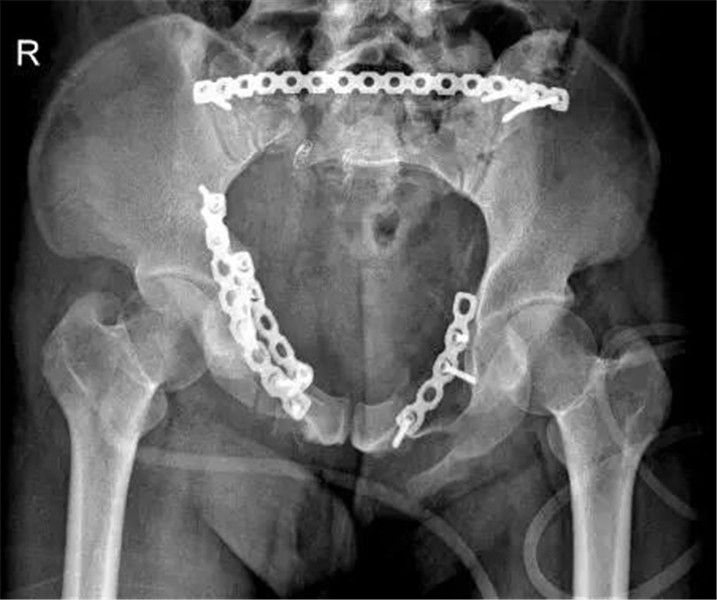

高处坠落后,男子骨盆骨折、腰椎骨折、失血性休克,三水人医多学科联合抢救成功

近日,一28岁男子从高处坠落致骨盆骨折、腰椎骨折,送至三水区人民医院急诊科时突然出现血压下降,四肢冰冷,血色素进行性下降等失血性休克表现,情况危急。经我院多科室紧急联合会诊、多次手术终于将患者救回。“急诊科抢救室01床急会诊,高处坠落伤,多...